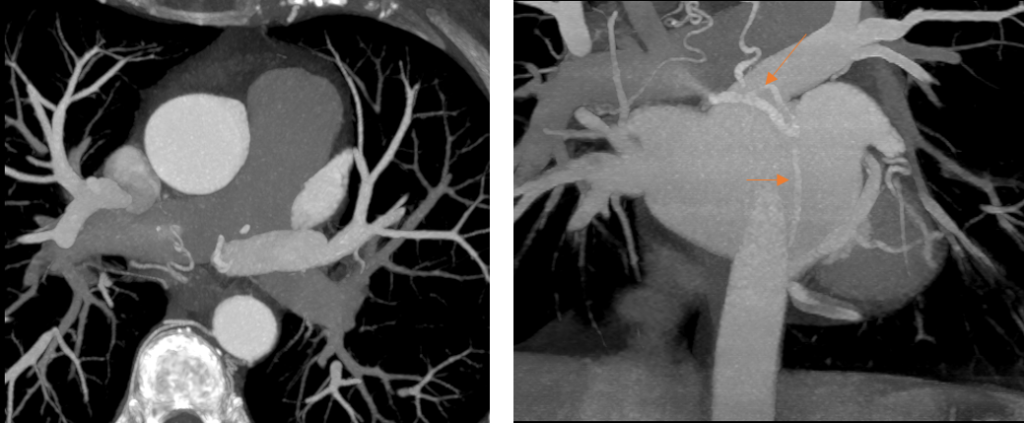

Figura 1: Fig 1 reconstrucţii multiplanare din achiziţie angioCT coronariană

Discuţie caz nr 50: Examinarea angioCT coronariană este actual indicație de clasa 1 la pacienții cu boală coronariană cronică; este cazul unui pacient care a fost diagnosticat la examinare angioCT cu fistulă între arteră coronară dreaptă și arteră pulmonară dreaptă.